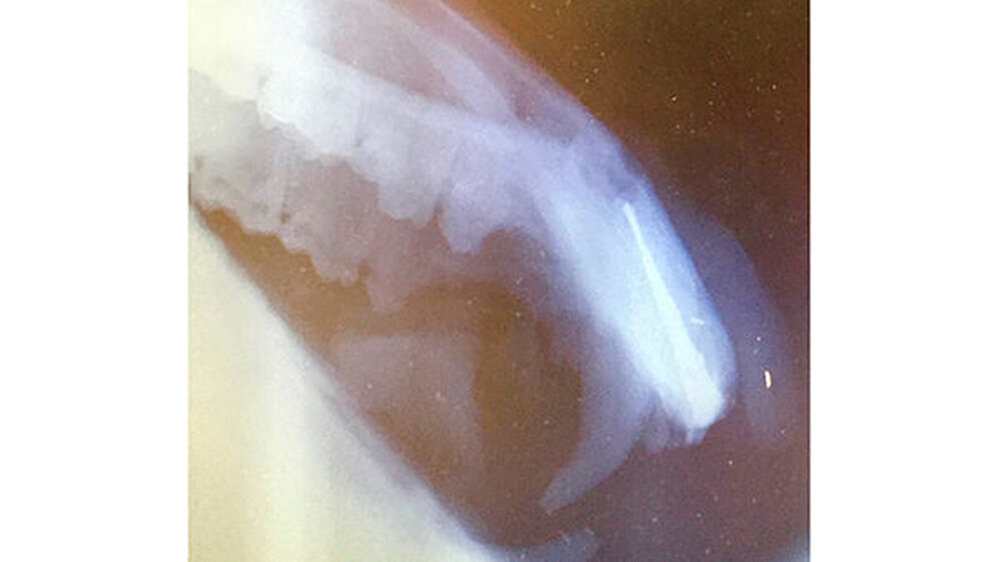

Drittens: Wurzelkanalbehandlungen an den Fangzähnen, den Dentes Canini, bedeuten aufgrund der extremen Länge von 70 bis 80 Millimetern bei großem Kanallumen eine enorme Herausforderung. Sie erfordern einen hohen Aufwand bezüglich der Darstellung und des „Flarings“ des gekrümmten Kanallumens mit Lindemannfräsen (60 Millimeter) und langen Wurzelkanalfeilen (75 bis 90 Millimeter), um die notwendige Arbeitslänge zu erreichen. Die elektrometrische Längenbestimmung funktioniert bei diesen Dimensionen nicht wirklich präzise, so dass man ohne eine Röntgen-Mess-Aufnahme zu einer fehlerhaften Längenabstimmung kommt.

Arbeitslänge: 80 Millimeter